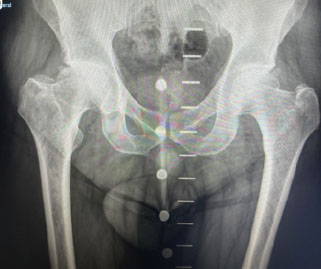

Ejemplo propio Prótesis Total de Cadera

Artrosis Cadera Derecha

Tonnis III